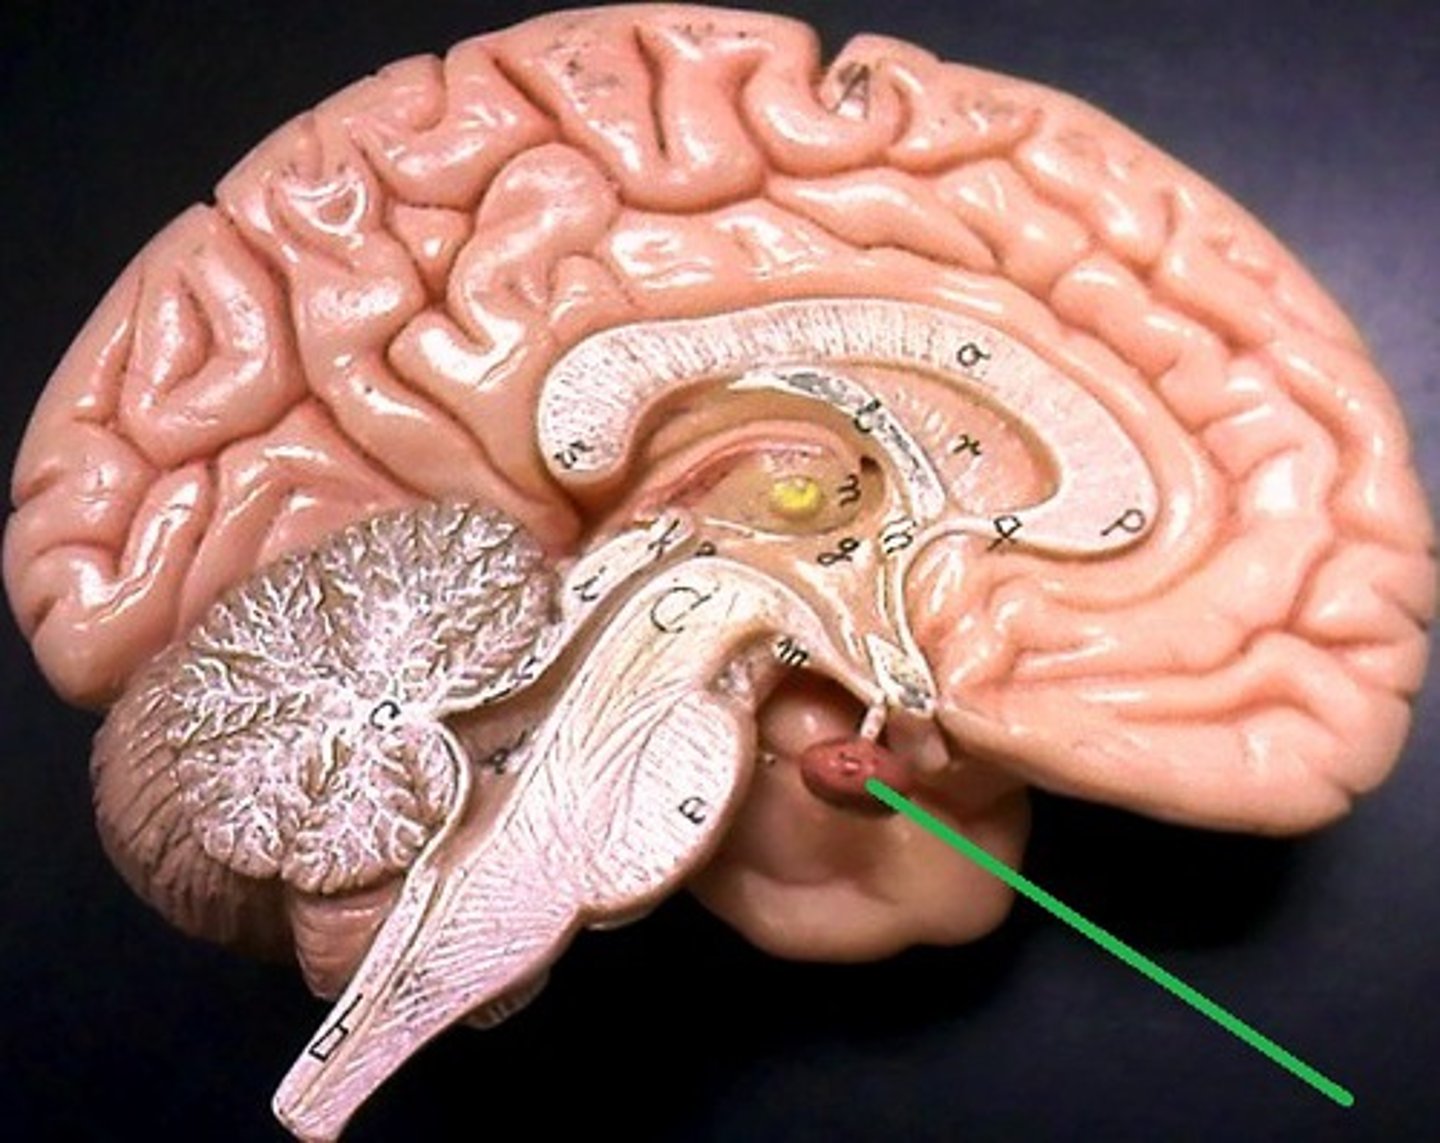

Diencephalon

Made up of 3 parts: the Thalamus, Hypothalamus, and Epithalamus

Epithalamus

Forms the roof of the 3rd ventricle,

Houses the pineal gland or body (an endocrine gland) (Melatonin production: sleep/wake cycle),

Includes the choroid plexus (forms cerebrospinal fluid- CSF)

Choroid Plexus

Forms Cerebrospinal Fluid

Choroid Plexus

Pineal Gland

Melatonin Production (sleep/wake cycle)

3rd Ventricle